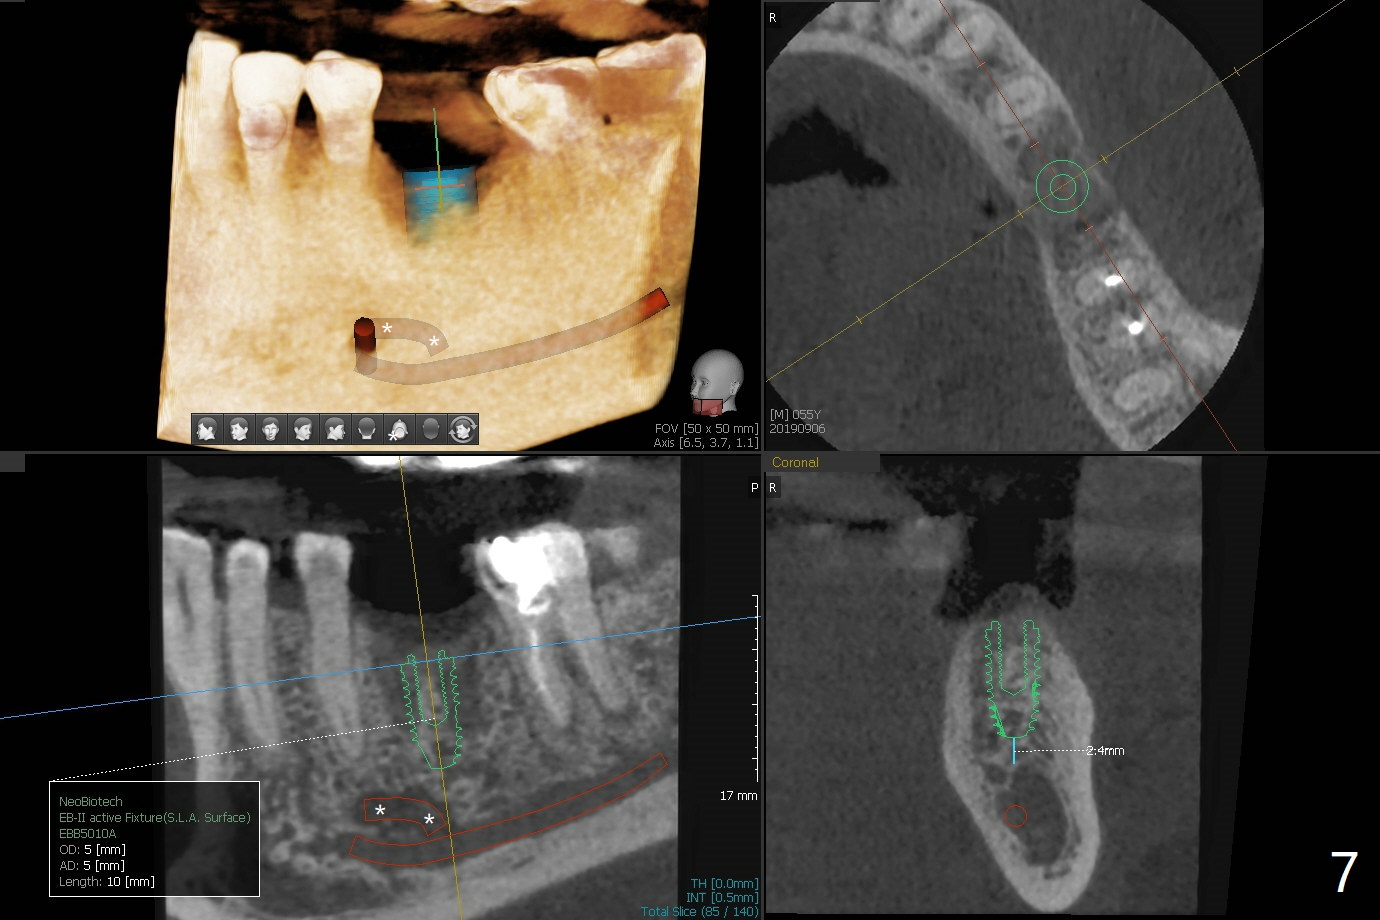

A 54-year-old man has several restoration with sign of bruxism (Fig.1). The tooth #19 has mesiodistal crack with furca radiolucency (Fig.2 *). To prevent abutment screw loosening associated with heavy mastication, a 6x17 mm tissue-level implant will be placed free hand due to the patient's tight schedule (blue, Fig.3,4,5). Pink: abutment; green: restoration which will be seated partially in the implant to reduce abutment loosening. To reduce possible neuropathy and have freedom to place implant deep, the implant length will be shorter, 14 mm, if the bone is dense. Take photos to show the crack line and buccal swelling. The patient returns for implant 4 months post extraction without bone graft in his home country with bone loss (Fig.6). In the presence of the accessory canal (Fig.7 *), a 5x10 mm implant is safe to be placed.